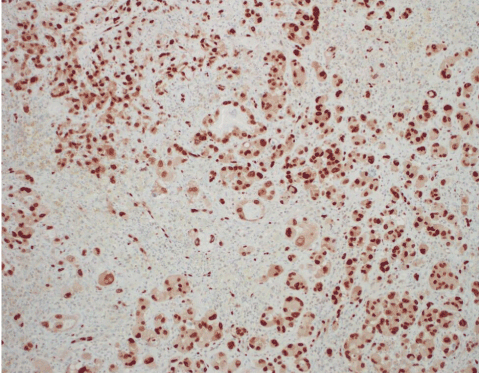

In 2010, Manner et al. [32] used array-comparative genomic hybridization and found high level amplification of chromosome 8q24.21 (corresponding to the gene MYC) exclusively in 55% of AS secondary to irradiation and chronic lymphedema, but not in primary AS. Studied cases included breast and non-breast sites. This study proposed that primary and secondary AS represent genetically distinct entities, though more recent studies have described examples of MYC amplification in primary cutaneous AS from various sites [33,34]. A later study further investigated the oncogenic role of MYC to include radiation-induced AVL, finding MYC amplification by fluorescence in situ hybridization (FISH) in 100% of secondary mammary AS and none in AVL, primary AS at any site, or in secondary sarcomas other than AS [29]. Importantly, when looking at excision specimens for AS, this study found MYC amplification only in the AS cells; no MYC abnormality was detected in AVL lesions seen adjacent to AS within the same mastectomy specimen. Fernandez and others reinforced these findings, showing MYC amplification by FISH in all cases of secondary AS but not in AVL [35]. Application of anti-MYC IHC showed strong positive nuclear staining in all cases of AS but none in AVL. Ginter et al. [33] found 100% concordance between MYC amplification and protein expression in AVL (negative), primary mammary AS (negative), and secondary mammary AS (positive). The staining pattern was moderate-strong and diffuse (>80% of neoplastic cells) in all positive cases, whereas complete absence of staining was seen in negative cases. When interpreting anti-MYC IHC, intervening benign capillary vessels should not be mistaken for non-immunoreactive neoplastic vessels, and it should be noted that lymphocytes can be positive for anti-MYC and may be problematic if they are so numerous as to obscure the vessels of interest. FISH for MYC amplification has a specificity of 100% and a sensitivity of approximately 80%, indicating that a negative result does not fully exclude a diagnosis of AS [35]. This is likely due to sampling or technical errors. FISH studies and anti-MYC IHC for AVL and AS are illustrated in Figures 12–19. Table 3 summarizes the findings of the studies to date regarding MYC amplification in primary mammary AS, secondary mammary AS, and AVL.

Figure 13. Corresponding anti-MYC IHC. Nuclear staining is strong and diffuse. MYC IHC, 148x.

Figure 12. AS. H&E, 144x.